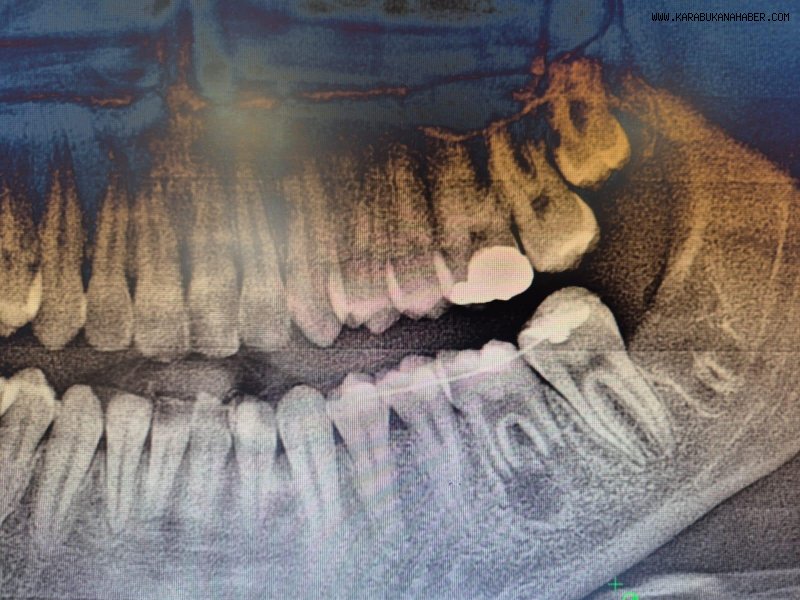

İleri düzey çürük nedeniyle daimi azı dişi çekilen hastaya, yaşı gereği çene gelişimi devam ettiği için klasik implant tedavisi uygun görülmedi. Bunun yerine, hastanın ağzında gömülü halde bulunan yirmi yaş dişi, uzman ekip tarafından cerrahi operasyonla çıkarılarak çekilen dişin yerine nakledildi.

Operasyon sırasında, dişin sağlıklı bir şekilde tutunmasını sağlamak için hastanın kendi kanından elde edilen PRF (Platelet Rich Fibrin) materyali, nakil öncesi hazırlanan diş yuvasına yerleştirildi. Bu uygulama, doku iyileşmesini hızlandıran ve hücre yenilenmesini destekleyen doğal bir yöntem olarak öne çıkıyor. Bu tedavi yöntemi, hastanın kendi dişi kullanıldığı için doğal görünüm, uyum ve fonksiyon açısından büyük avantaj sağlıyor. Aynı zamanda, vücut tarafından kabul edilme oranı yüksek olduğundan, uzun vadeli başarı şansı da oldukça yüksek.

Operasyon, Karabük Üniversitesi Diş Hekimliği Fakültesi Endodonti Anabilim Dalı Öğretim Üyesi Doç. Dr. Olcay Özdemir ve Ağız, Diş ve Çene Cerrahisi Anabilim Dalı Öğretim Üyesi Dr. Öğr. Üyesi Muhammed Abdullah Çege tarafından başarıyla gerçekleştirildi.